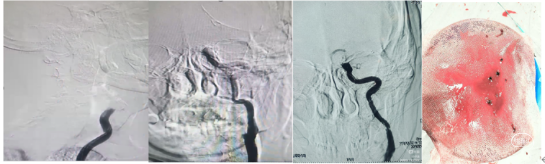

8Fguiding到达C1段支撑070银蛇中间导管裸奔边上行边抽吸,抽出部分血栓,造影显示到血流达到C6段。

术中边推进导管边抽吸,抽出部分血栓,造影显示到血流达到C6段。

1、微导管到位:微导丝通过M1段艰涩困难,再次偿试通过M1段到达M2。携带微导管到达M2段,微导管造影显示远端有正向血流,在真腔内。下图1

2、支架释放:通过027微导管释放6X30mm 通桥蛟龙支架,静置5分钟后微造影,大脑中未显影,未见首过效应考虑血栓负荷较大。大脑前有血流。下图2

3、裸支架导丝技术:缓慢撤出微导管于体外,裸支架导丝,保留中间导管最大管腔。

4、中间导管收拢支架尾部一体回撤:中间导管跟进至M1段收拢支架尾部下,负压踹马桶抽吸中间导管,缓慢一体回撤支架和中间导管,一次取出长约3.5cm黯红色血栓。

5、二次抽吸清理:迅速清理导管进行二次抽吸未抽吸出肉眼血栓。

造影显示:

大脑中动脉畅通,远端血流达3级。但分叉以远分支似有少量血栓。考虑6x30m支架放置M2段过大,未再进行远端分支取栓,经导引导管给予替罗非班6ml推注。结束手术。